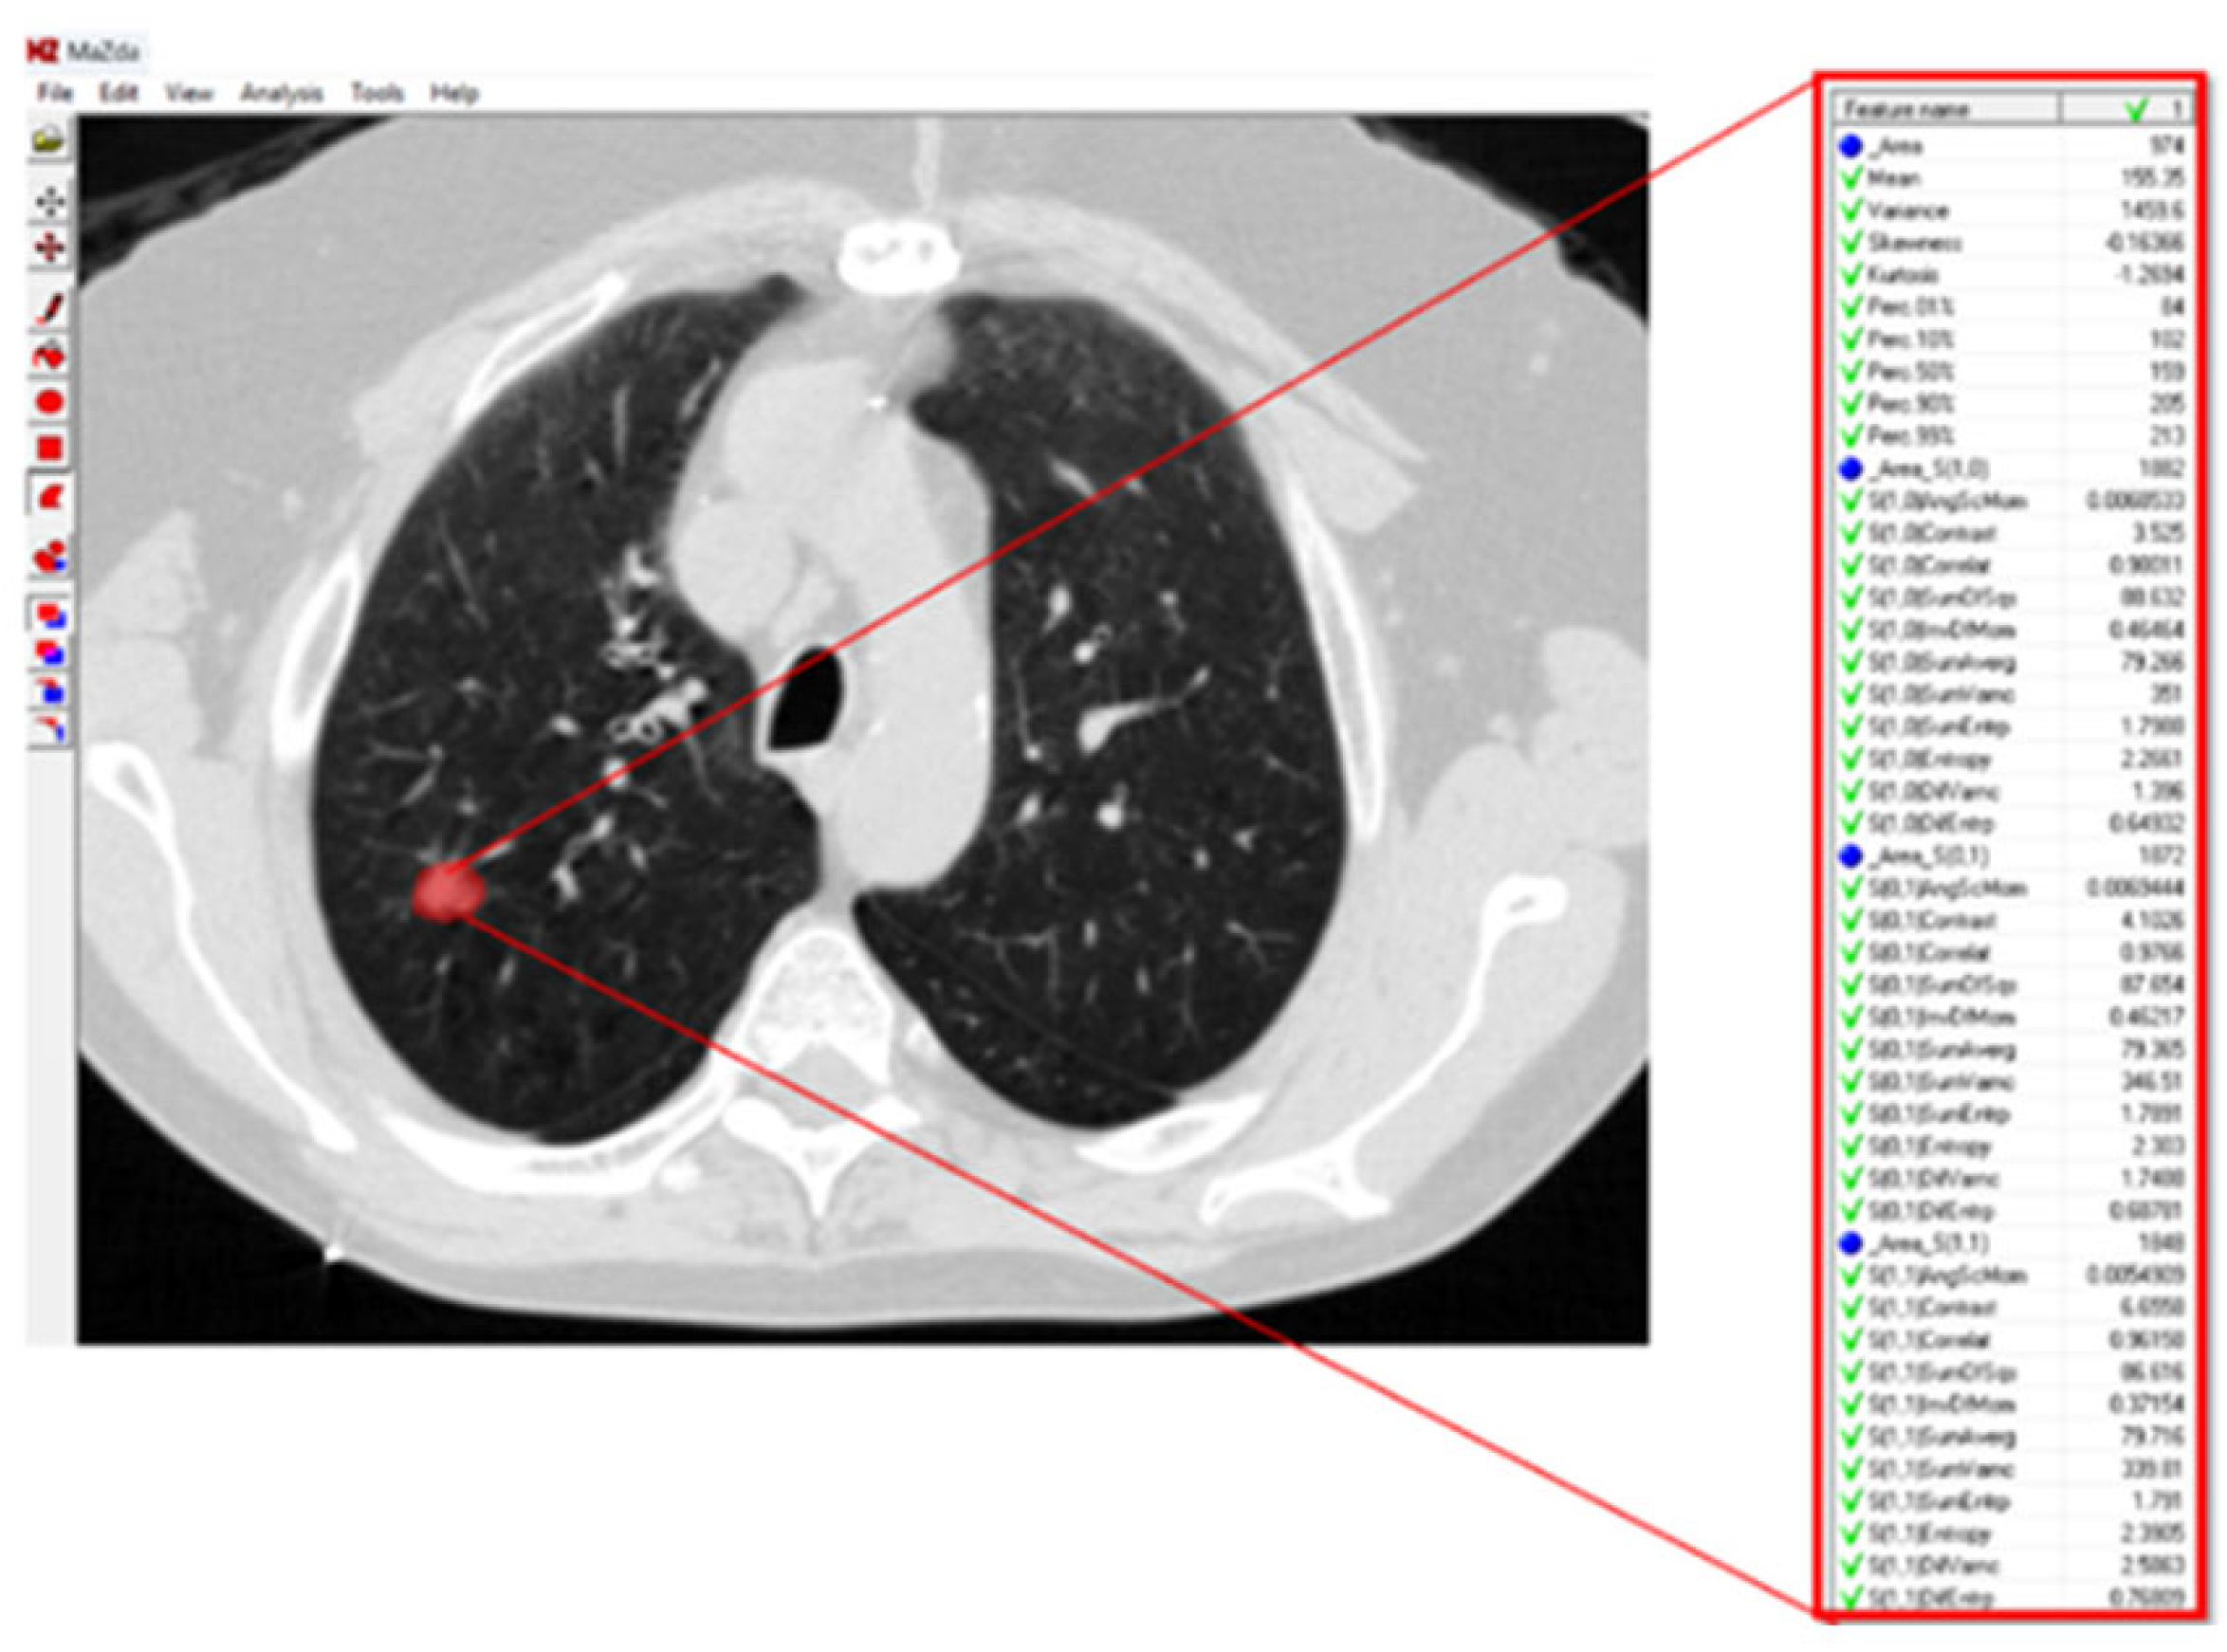

For texture analysis, a digital technology called MaZda (version 4.6) was used [27]. To calculate the texture variables of the GGO lesions in the radiographic image, an annotation of the tumor region was performed. Subsequently, the software calculated the texture variables (Figure 1).

Figure 1. Lung CT scan with ground-glass opacity (GGO). The GGO lesion is marked with a circle, and the pixel matrix shows the tumor texture. A zoomed-in view of the grayscale pixel intensities used for texture analysis. In this matrix, grayscale values are integers that range from 0 (black) to 255 (white), allowing for the analysis of the texture of the pixels that make up the tumor and the stroma accompanying the tumor.

Jcm 14 08082 g001

Figure 2. Lung CT scan with GGO texture analysis. About one-third of the variables extracted by the MaZda 4.0 software for the texture analysis of the GGO in this lung CT scan are presented. The red circle denotes the GGO region of interest.

Jcm 14 08082 g002